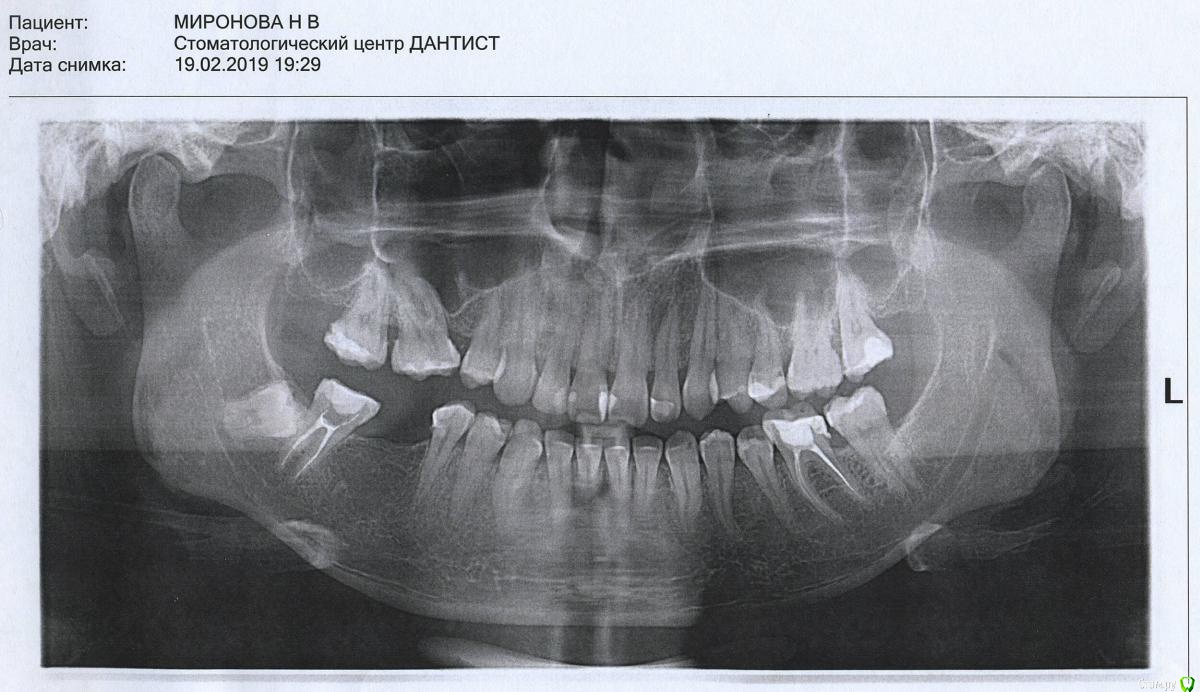

DmitrySH Опубликовано 15 февраля, 2019 Поделиться Опубликовано 15 февраля, 2019 Здравствуйте, а есть возможность нам снимок показать? Ссылка на комментарий

nataganka Опубликовано 18 февраля, 2019 Автор Поделиться Опубликовано 18 февраля, 2019 Здравствуйте, а есть возможность нам снимок показать?Здравствуйте, снимки смотрели при мне на компьютере, распечатку не давали (консультации бесплатные были в обоих местах). Но я могу зайти сделать снимок снова в ближайшей к дому стоматологии, подскажите какой снимок сделать для этой темы, ортопантомограмма или снимок 47 зуба прицельно? Ссылка на комментарий

red_butler Опубликовано 18 февраля, 2019 Поделиться Опубликовано 18 февраля, 2019 подскажите какой снимок сделать для этой темы, ортопантомограмма или снимок 47 зуба прицельно? панораму Ссылка на комментарий

nataganka Опубликовано 20 февраля, 2019 Автор Поделиться Опубликовано 20 февраля, 2019 Ссылка на комментарий

Pavel-Pskov Опубликовано 20 февраля, 2019 Поделиться Опубликовано 20 февраля, 2019 Конечно надо очный осмотр, но как то не вижу показаний к обширной костной пластике. И скорее всего мостовидный протез из ДЦ должен быть не сильно дешевле импланта, не говоря уже о травме здорового зуба, но это всё, повторюсь, по фото и по снимку. Ссылка на комментарий

DmitrySH Опубликовано 20 февраля, 2019 Поделиться Опубликовано 20 февраля, 2019 Если ориентироваться на снимок, то 47 можно восстановить пломбой и обойтись и керамической реставрацией Ссылка на комментарий